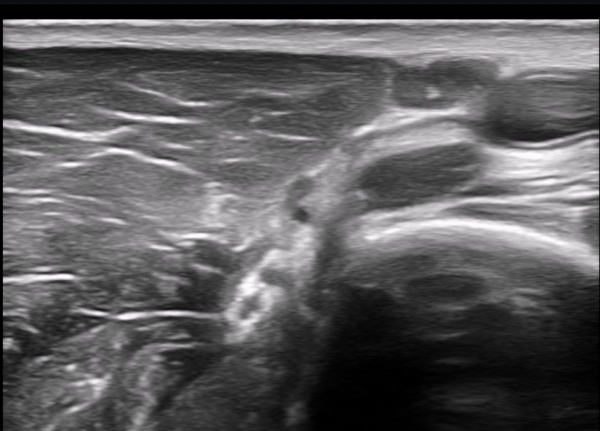

±ÙÀ°ÇǺνŰæÀÇ Á¾´Ü¸é°Ë»ç¿¡¼­ ±ÙÀ°ÇǺνŰæÀÇ ±¹¼ÒÀû ÇùÂø°ú ±ÙÀ§ºÎÀÇ Àú¿¡ÄÚ ºÎÁ¾ÀÌ °üÂûµÈ´Ù

(»çÁø 4, 5, 6,7) À̰ÍÀº ½Å°æÀÇ ¿°Àü(torsion)¿¡ ºÎÇÕÇÏ´Â ¼Ò°ßÀÌ´Ù.